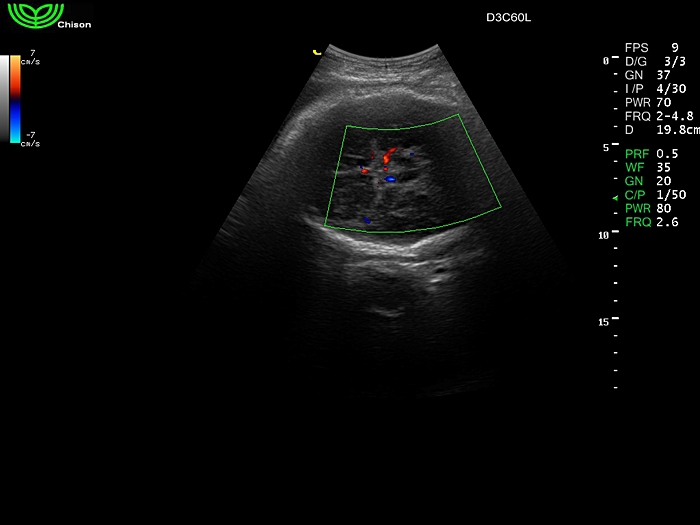

D3C60L 3.5МГц, конвексный.

2.0МГц - 5.8 МГц. Применения: абдомиальное обследование, акушерство, гинекология, обследование районной блокады нерва, осуществление и управление биопсией. |